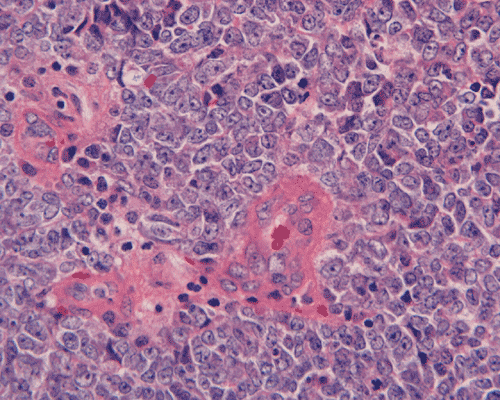

Pathology of the case:

The surgery removed several irregular fragments of tan, soft tissue for examination that were 2.5 x 1.2 x 1.0 cm in toto. Histologically, the lesion is a highly cellular neoplasm with tumor cells packed in solid sheets and without a specific architectural pattern (Panel D). Small, focal necrosis is also present (not shown). The tumor has rich vascularity and the endothelial cells seem to be active (Panel E). Almost all the tumor cells have only a thin rim of amphophilic cytoplasm, large nuclei with prominent nucleoli (Panel E and F). Clear cytoplasm is present in some tumor cells. In general, the cells do not look epithelioid or spindle. In some of the tissue fragment, the tumor shows invasion into the peripheral nerve root with dissection of the nerve fibers (Ú in Panel G and H). This phenomenon is well demonstrated by reticulin stain (Panel I) and immunohistochemistry for neurofilament proteins (Panel J). About half of the tumor cells are strongly positive for vimentin (Panel K). There is also scant positive tumor cells for S100 protein (Panel L) and cytokeratin AE1/3 (Panel M). The tumor cells are negative for neuorfilament proteins (Panel K) and smooth muscle protein (Panel N).